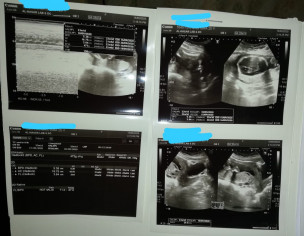

What this report says? Do you think there is some contradiction so that I should repeat a scan?

PS: Not having any bleeding and water leaking issue.

All normal

Wat abt liqor??? Its normal?

Repeat ultrasound after 2weeks from some other doctor